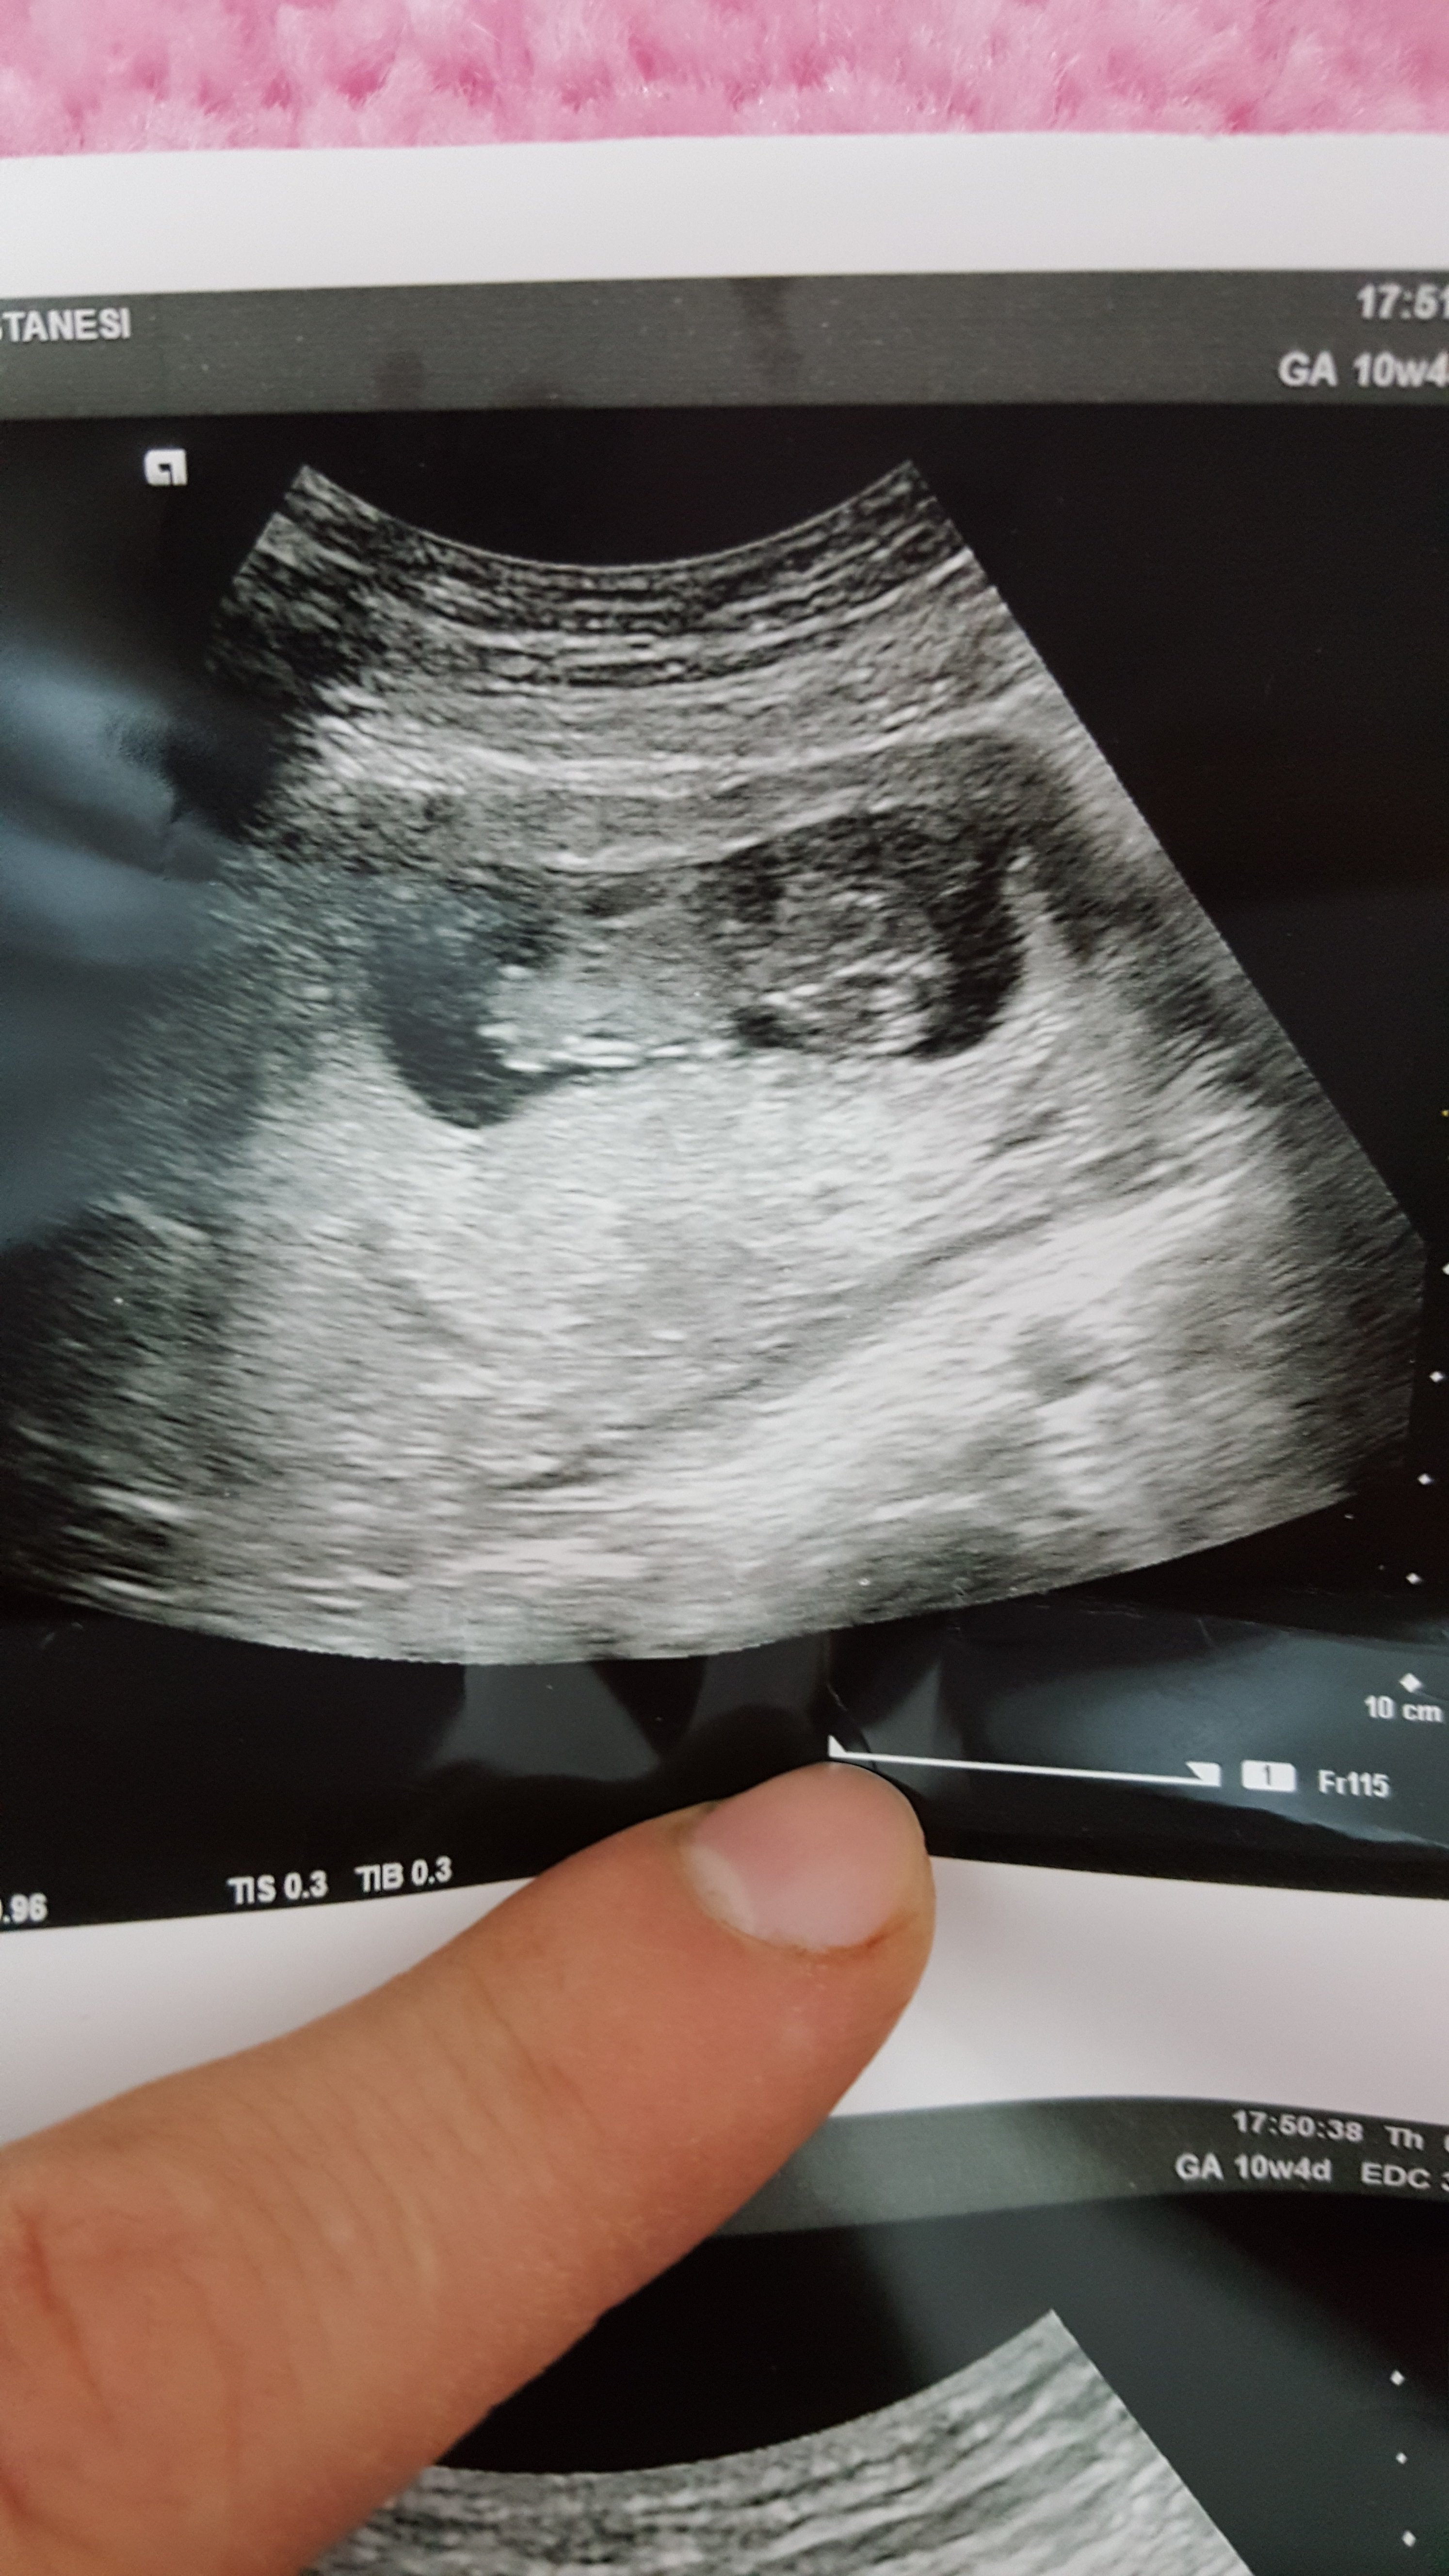

R rma_rma Yeni Üye Üye 7 Ocak 2017 #117 buda benim bebegim 13 haftaligiz .yorum yaparmisiniz rica etsem🙂

Sevimli cadı Daimi Üye Üye 8 Ocak 2017 #120 rma_rma' Alıntı: Ekli dosyayı görüntüle 73270 buda benim bebegim 13 haftaligiz .yorum yaparmisiniz rica etsem🙂 Genişletmek için tıkla ... Sizin bebeğinizin cinsiyeti kız 🙂

rma_rma' Alıntı: Ekli dosyayı görüntüle 73270 buda benim bebegim 13 haftaligiz .yorum yaparmisiniz rica etsem🙂 Genişletmek için tıkla ... Sizin bebeğinizin cinsiyeti kız 🙂